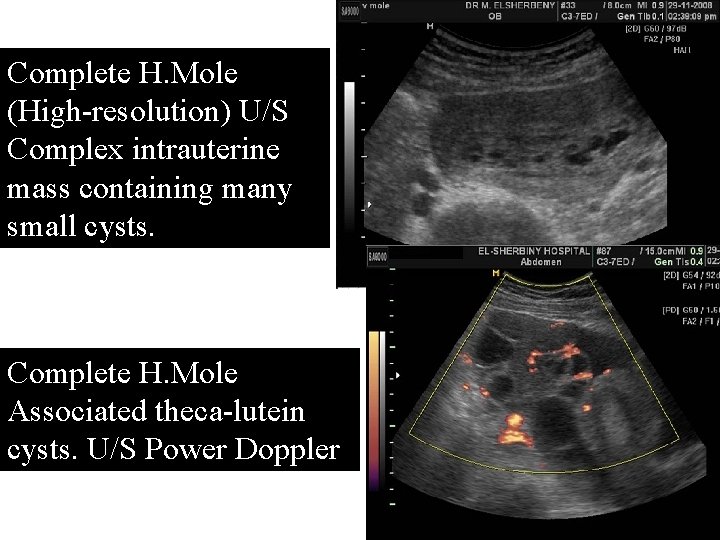

Complete H. Mole (High-resolution) U/S Complex intrauterine mass containing many small cysts. Complete H. Mole Associated theca-lutein cysts. U/S Power Doppler

Hysterectomy may be preferred to suction curettage at age ≥ 40 with no desire for further pregnancies especially with other risk factors for GTN as : Ø Large theca lutein cysts( >6 cm) Ø Significant uterine enlargement Ø Pretreatment βh. CG ≥ 105. Although hysterectomy does not eliminate possibility of GTN this, it markedly reduces its likelihood. Soper. Obstet Gynecol 108: 176, 2006 Garner Up. To. Date 2010 Cunningham et al, Williams Obstetrics, 23 ed , 2010

Complete H. Mole with large for date uterus& Theca-lutein cyst Patient was 42 years 5 th G P 5 initial Bh. CG: 195, 000 m. IU/m. L Complete H. Mole After Hysterectomy

Theca-lutein cyst associated with a complete H. mole in >30%